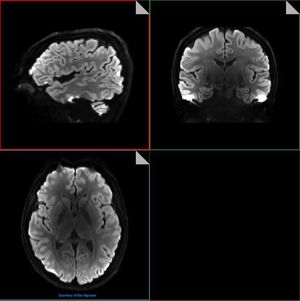

Simultaneous Multi-Slice (SMS) speeds up imaging significantly through the simultaneous excitation and readout of multiple slices, helping cut neuro DWI scan times by as much as 68%. Figure 1.2mm isotropic DWI b1000 (90slices) acquired in axial plane. MPR in sagittal and coronal plane. Images courtesy of Nguyen Bac.